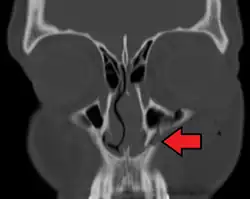

- the maxillary sinus

A maxilla fracture is a form of facial fracture. A maxilla fracture is often the result of facial trauma such as violence, falls or automobile accidents. Maxilla fractures are classified according to the Le Fort classification.